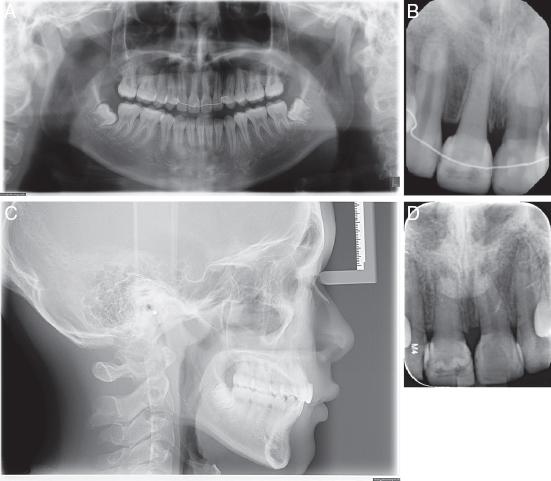

As a result of the trauma, the upper right central incisor (#11) was missing. The upper left central incisor (#21) and upper right lateral incisor (#12) were root canal treated and showed clinical and radiographic signs of ankylosis and replacement resorption (Figure 2A-D).

(A) Pretreatment dental panoramic radiograph. (B) Periapical radiograph showing resorption on the apical surfaces of #12 and #21. (C) Lateral cephalogram. (D) CBCT section showing developing tooth #45 with ¾ root length.